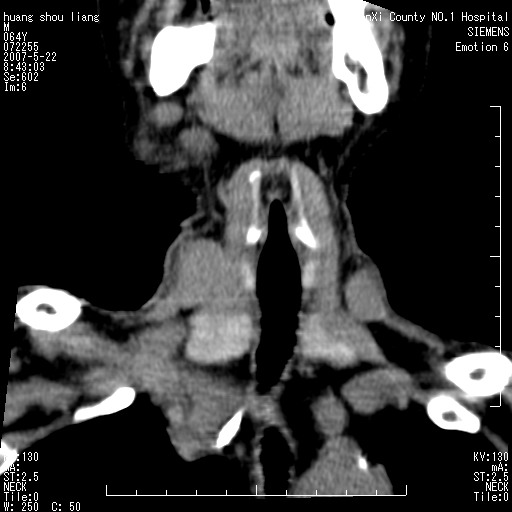

男性,64岁。颈部包块8年。最近增大。

对不起大家,可能是片子发太多有点乱,正常腮腺在下颌角的外侧,颌下腺在下颌体的中部内侧,本例在下颌角内侧偏下,和腺体一点关系都没有,从vrt和mpr上可以很明显看出来,再者肿块是好多粘连在一块的,大家在仔细看看,左侧可能也是吧,我还是考虑为肿大的淋巴结融合在一块,但性质??????

右侧腮腺下部均匀软组织密度肿块,外形不规则,与周围组织分界清晰,考虑右侧腮腺混合瘤或多形性腺瘤。

大家好,病理结果出来了,如大家所说,颌下腺混合瘤。

唉,解剖没学好吧,我诊断错了,不过还是有些不理解回去我在多看看书,谢谢大家的参与,以后我还会奉献好的病例。